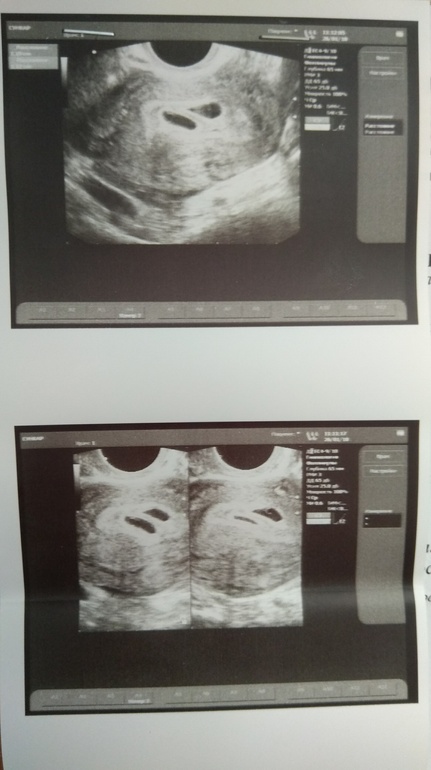

Наше первое УЗИ. Параметры СВД

26 января поехали на УЗИ. Два плодных яйца, но эмбрионов пока не увидели. Пойду 10 февраля на повторное УЗИ на наличие эмбрионов. Не могу понять..Прочитала в интернете, что СВД 11 мм соответствует 6 неделям. По месячным сейчас 7 недель,а по УЗИ - 4 недели. Кто-нибудь с таким сталкивался... Когда у Вас увидели на УЗИ два эмбриона и слышно было сердечки? И какое было СВД на этом сроке? Уже дни считаю до УЗИ. И молюсь, чтобы все было хорошо.